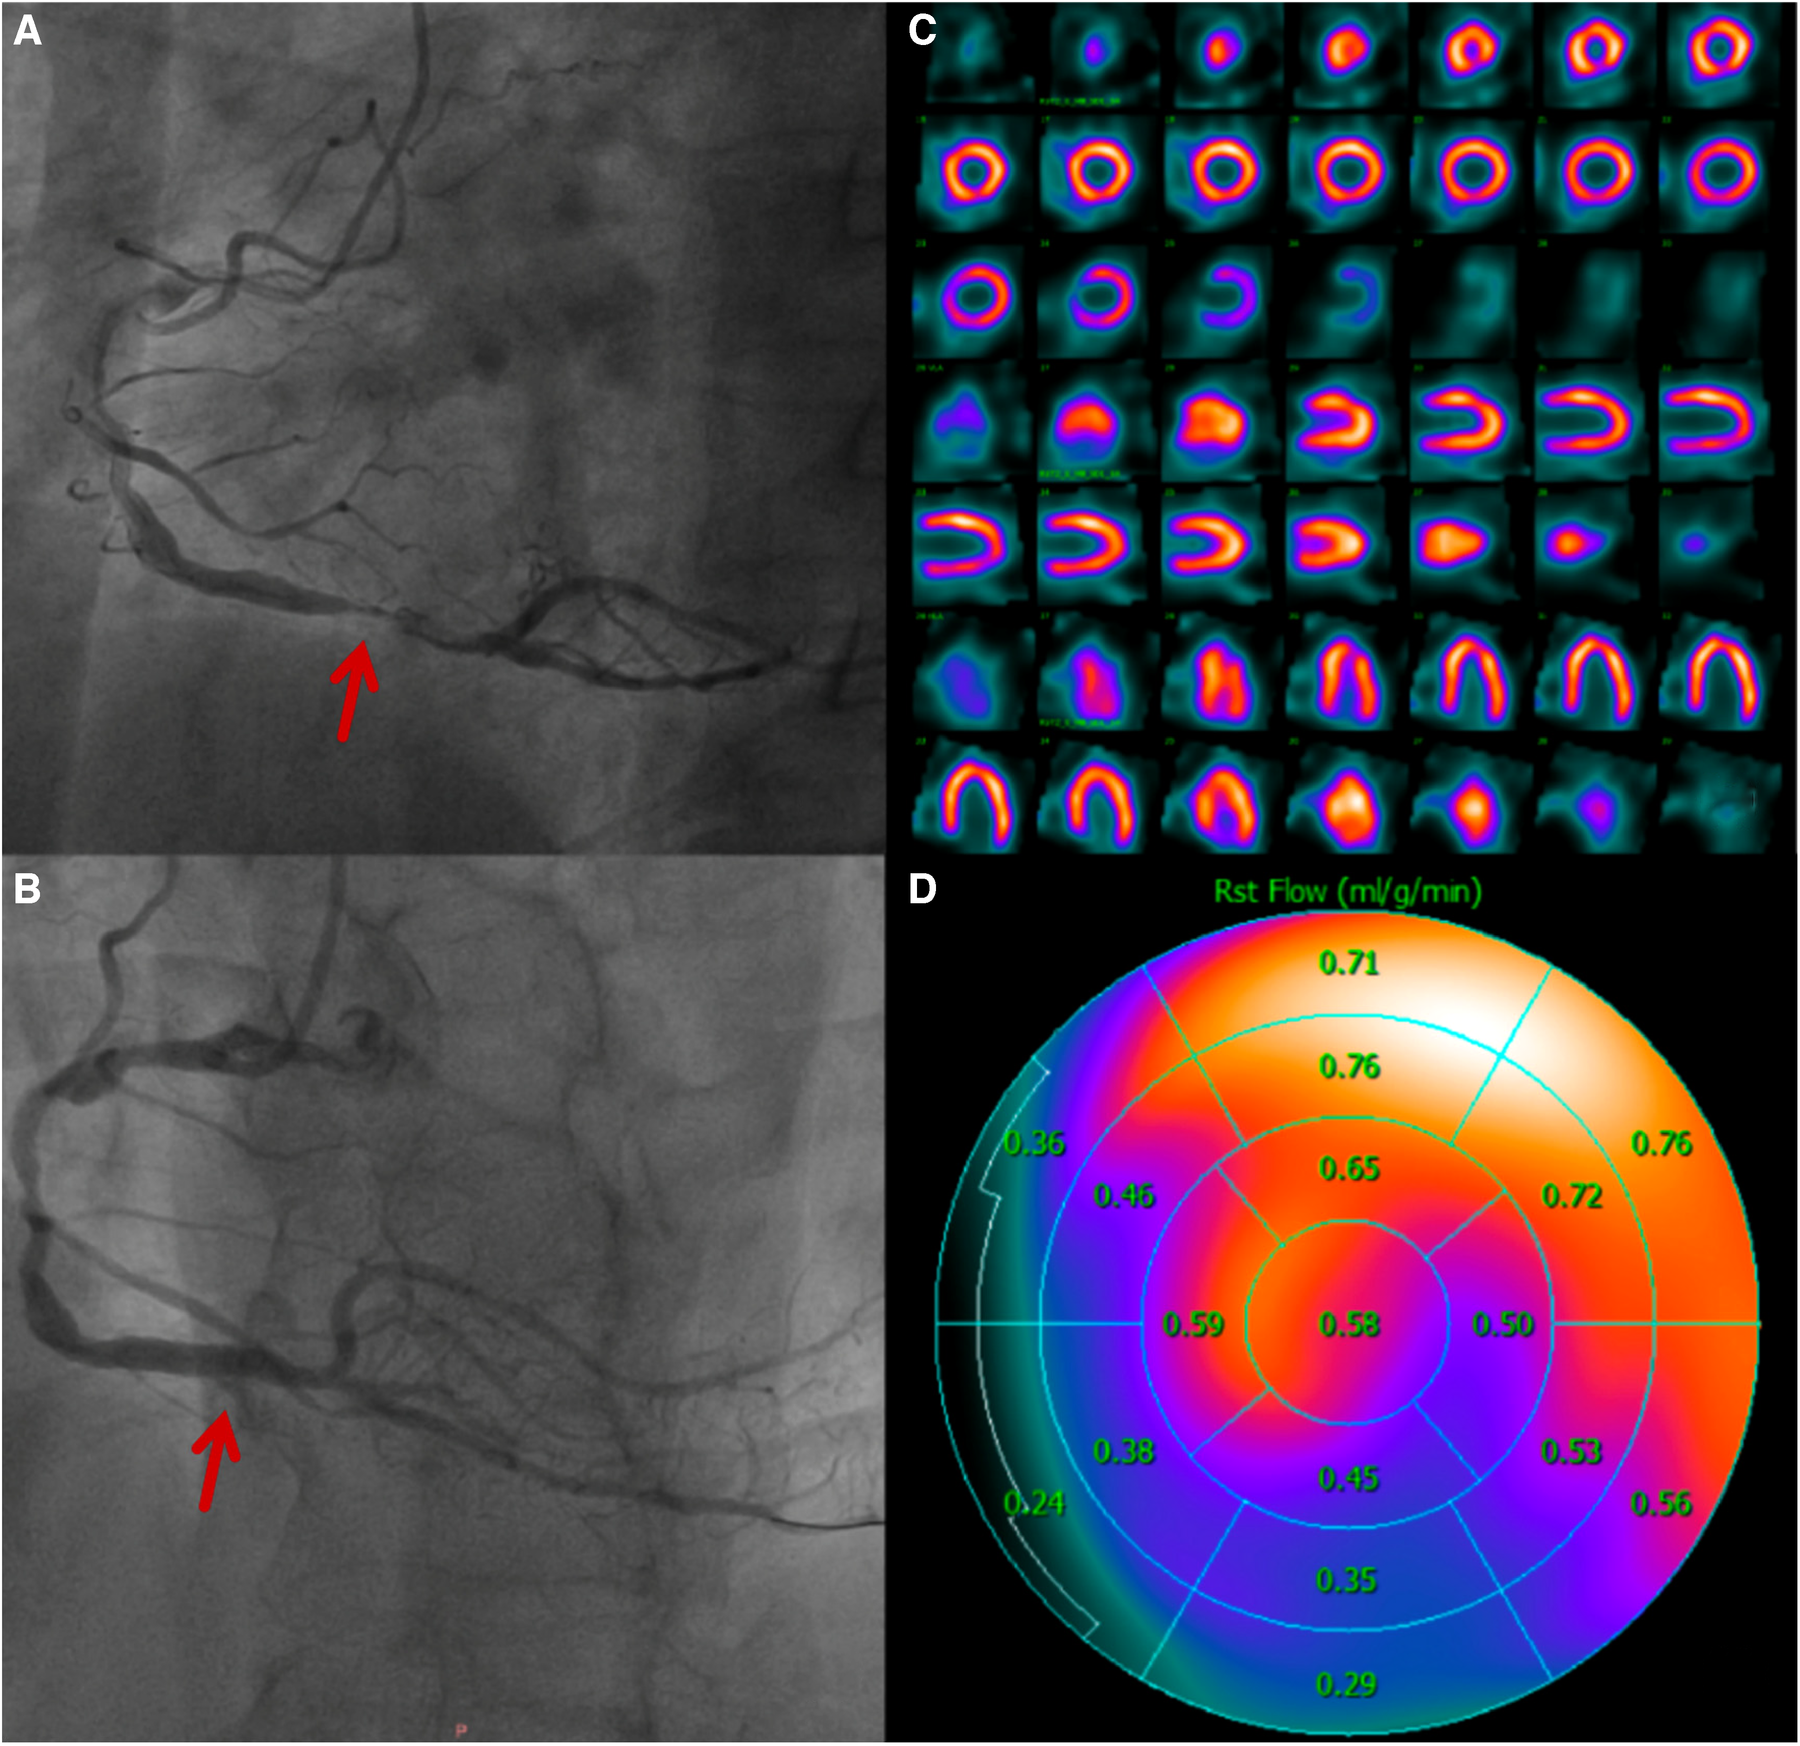

Figure 5

A 60-year-old man who was diagnosed with acute inferior ST-elevation myocardial infarction. 1.5 h after the onset of the disease, drug thrombolytic therapy was administered, the patient's clinical symptoms were alleviated, and his ST segment decreased by more than 50%. He entered the cath lab 11 h after the onset of illness. (A) CAG showed that the main lesion was located in the distal RCA posterior anterior trigeminal tubular, and approximately 95% of the stenosis and thrombosis was visible. (B) CAG after PCI, balloons placement and medication treatment. (C) After 4 days of treatment, there was normal in resting MPI. (D) Resting MBF showing that the RCA blood supply area was significantly lower than that in other regions.